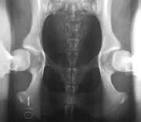

The radiographs pictured here are of the same

dog, yet the hip joint laxties in each view look

very different. Notice that the hips in the distraction view

appear to be much looser than they do in the hip-extended view.

The obvious contrast in joint laxity

between the distraction and hip-extended views

demonstrates the fundamental difference between the two

radiographs. The

looser the joint on the distraction view, the greater is

the chance that the hip will develop OA.

The hip-extended view tends to mask true hip joint

laxity because the joint capsule iswound up into

a tightened orientation when the hips are extended. This

explains why measurable joint laxity on the distraction

view is always greater than the measurable laxity from

the hip-extended view. In fact, distraction laxity is up

to 11 times greater depending on the breed of dog under

study. The compression view is used to determine the "goodness of fit" of the femoral heads into the acetabula. In a hip with OA, the remodeling that occurs in the acetabulum and/or the femoral head, will often result in an ill-fitting "ball" and "socket". |